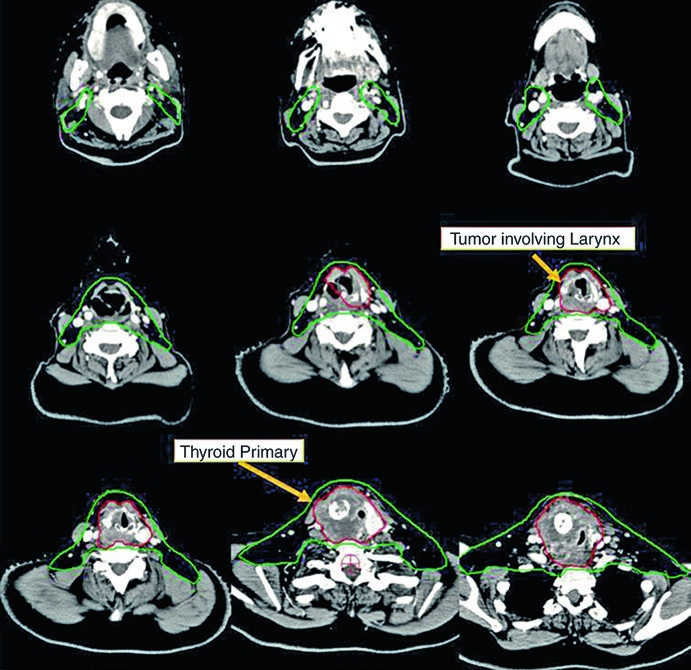

Dois dos cinco casos ilustrativos do livro de referência demonstram o manejo de doença irressecável tratada com quimiorradioterapia definitiva. Ambos receberam plano IMRT com dose-painting simultâneo.

Caso 2 — Carcinoma anaplásico irressecável (Fig. 9.2): Mulher de 73 anos com carcinoma anaplásico de tireoide invadindo laringe, traqueia e esôfago. Recebeu quimiorradioterapia definitiva com doxorrubicina concomitante. O CTV70 Gy (vermelho) engloba toda a doença volumosa, e o CTV60 Gy (verde) abrange o risco subclínico. Detalhe importante: o manúbrio, que normalmente não é incluído no volume de risco, foi englobado neste caso específico por conta da doença volumosa anterior agressiva no pescoço. Essa decisão é atípica e deve ser individualizada — não se trata de protocolo, mas de resposta a uma apresentação clínica particular.

Esses dois casos ilustram a versatilidade da IMRT com dose-painting: o plano entrega simultaneamente 70 Gy ao volume de alto risco e 60 Gy ao volume subclínico, sem necessidade de boost sequencial. A escolha de doxorrubicina como quimioterápico concomitante no anaplásico reflete a agressividade dessa histologia e a necessidade de sensibilização ao tratamento, embora as opções sistêmicas tenham evoluído significativamente nos últimos anos.